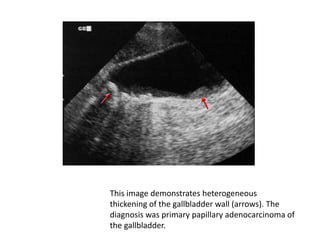

This image demonstrates heterogeneous

thickening of the gallbladder wall (arrows). The

diagnosis was primary papillary adenocarcinoma of

the gallbladder.